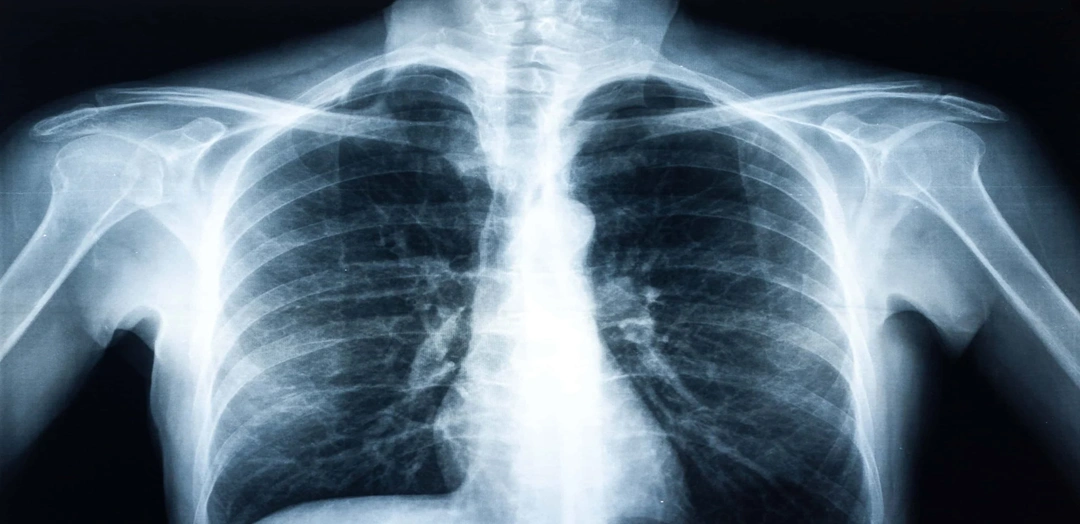

The Chest PA View X-Ray Test is a non-invasive, painless imaging test used to examine the structures inside the chest, including the lungs, heart, ribs, trachea, and blood vessels. PA stands for Posterior–Anterior, which means the X-ray beam passes from the back of the chest to the front for clearer imaging.

This view gives the most accurate representation of lung fields and heart size, making it the standard diagnostic view for chest evaluation.

A Chest PA View X-Ray is a standard diagnostic imaging test used to detect structural abnormalities inside the chest, such as those involving the lungs, heart, ribs, and blood vessels.

In the Posterior–Anterior view, the X-ray beam passes from the back of the chest to the front, producing a clear and accurate image of lung fields and cardiac size. This view minimizes heart magnification and gives a realistic chest anatomy image.